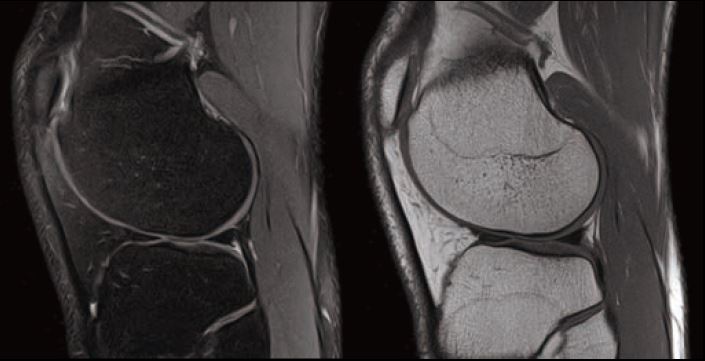

Випадок 1. Велике коліно

Жінка 67 років скаржиться на постійний медіальний біль у коліні.

• Відносно рясний внутрішньосуглобовий випіт.

• Остеоартритне ураження стегново-гомілкового суглоба в медіальній частині зі змінами субхондральної кістки, що може відповідати стресовому перелому.

• Дегенеративна сторона заднього рогу медіального меніска.

Рис. 1 Sg T2 FS, товщина зрізу 3 мм, роздільна здатність 0,4 мм.

Рис. 2 Sg FSE T1, товщина зрізу 3 мм, роздільна здатність 0,4 мм.